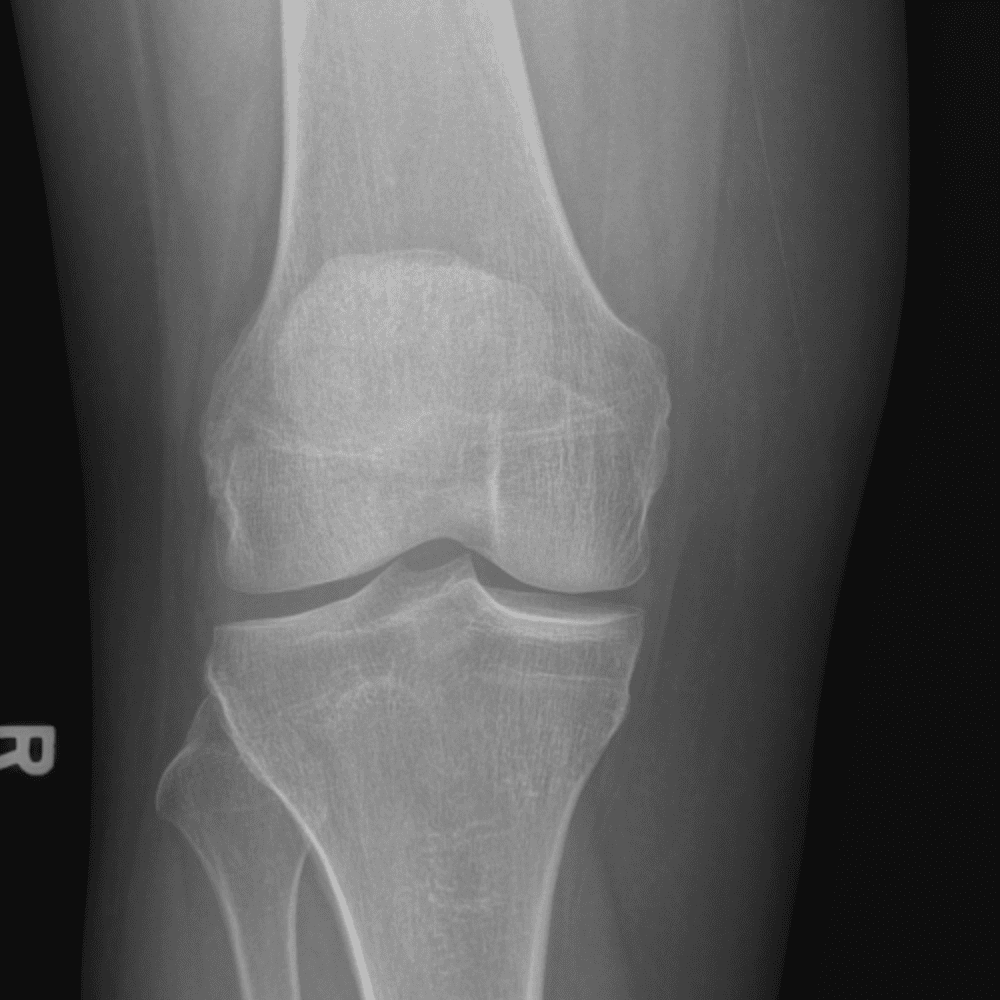

Simula o plantão incluindo casos sutis ou difíceis e alguns normais.